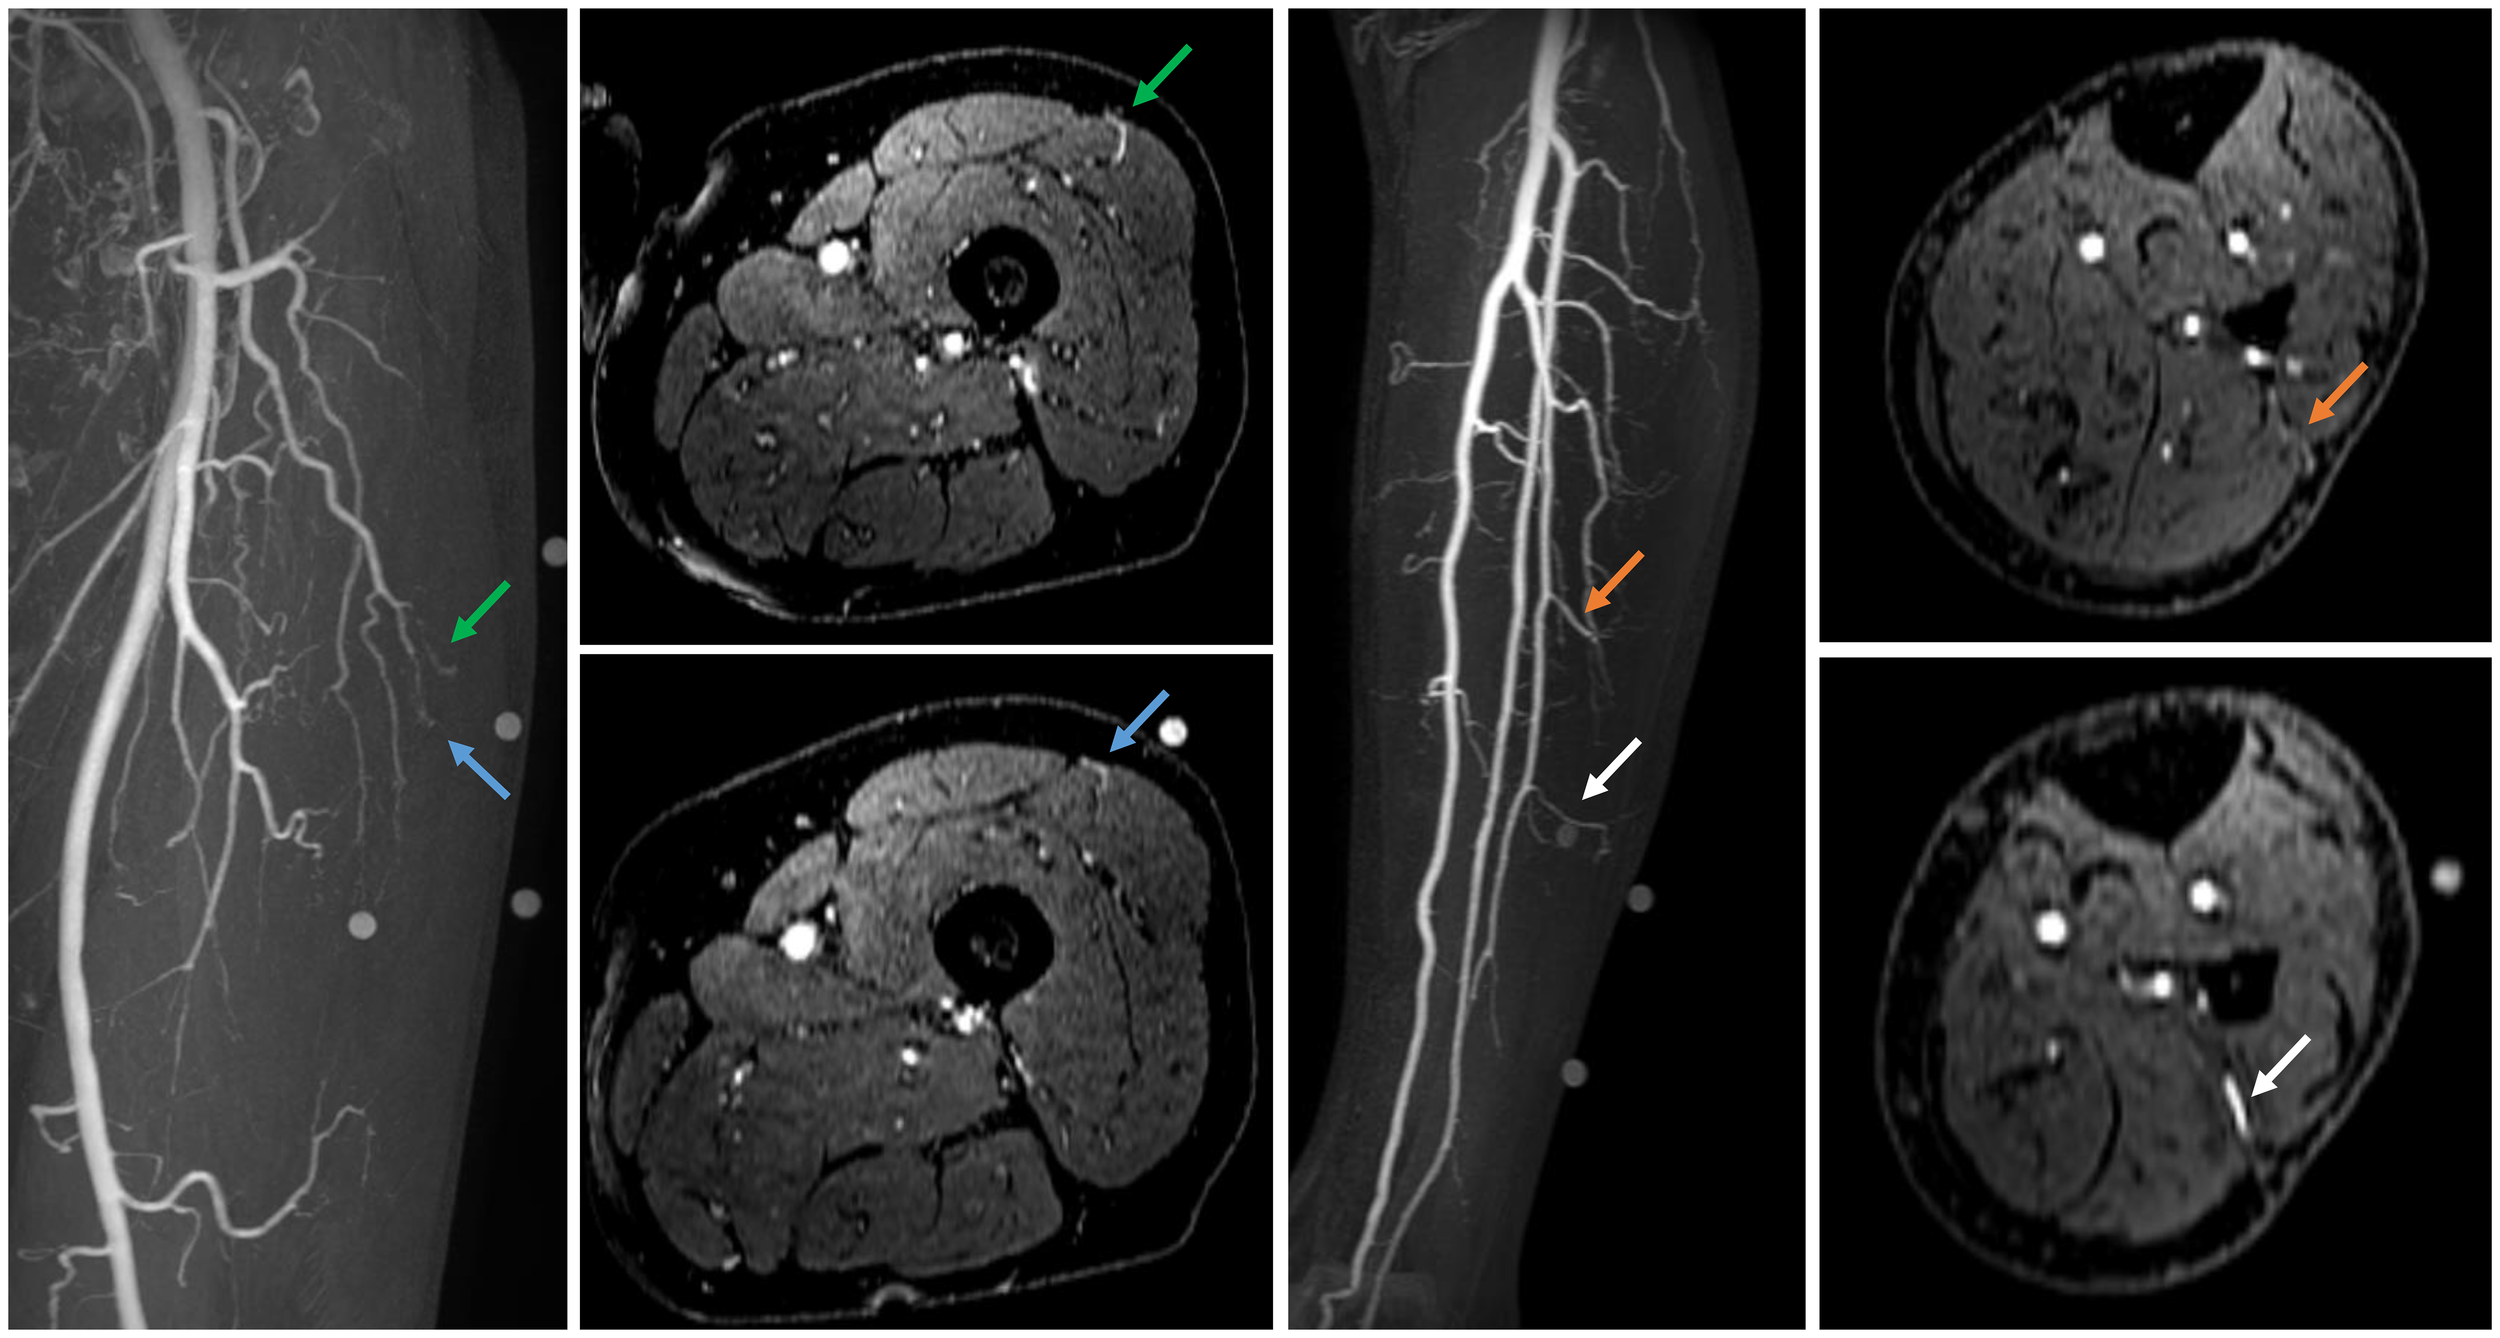

Centra k-space acquisition is used for contrast filling, starting two seconds after fluoroscopic triggering. For optimal perforator filling in the head and neck cancer patient population, the arterial mDIXON scan is triggered when vascular images are seen as shown in Figure 3. For ALT patients, branching of the lateral circumflex femoral artery (LCFA) is visible and contrast fills half of the upper leg. For MSAP and FFF patients, the popliteal trifurcation is visible and contrast fills the upper third of the lower leg. Figure 4 displays examples of arterial mDIXON Maximum Intensity Projection (MIP) images alongside corresponding axial slices, illustrating visible perforators in patients scheduled for surgery with ALT and FFF reconstruction.

Figure 4. Contrast-enhanced mDIXON arterial Maximum Intensity Projection (MIP) images with corresponding axial slices, in which perforators are indicated by arrows. The left panel shows the upper leg for the anterolateral thigh flap, while the right panel depicts the lower leg for the fibula free flap.